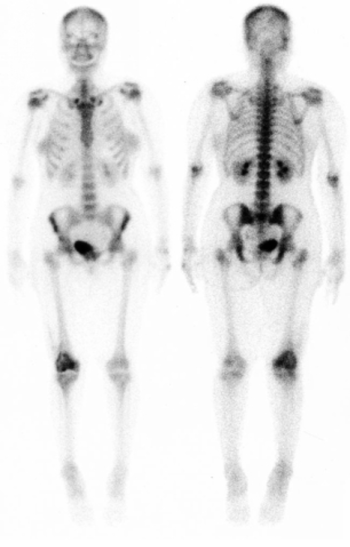

Csontvizsgálat.